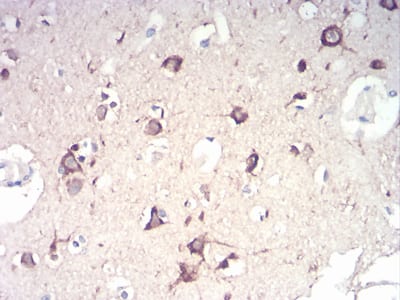

Immunohistochemical analysis of paraffin-embedded human brain tissues using NFKBIA mouse mAb with DAB staining.